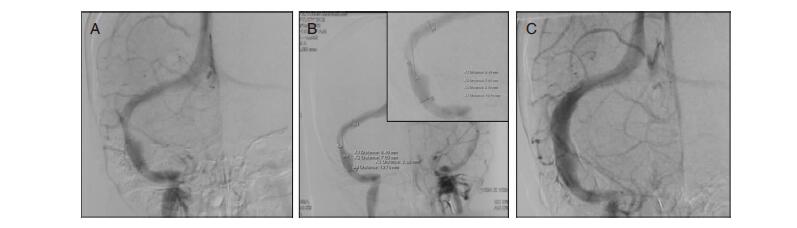

| 图 2 脑血管DSA所示。A:左侧乙状窦狭窄;B:狭窄处经测量长度约为19.76 mm;C:行支架植入术后狭窄显著改善。 |

入院后两次行腰椎穿刺,脑脊液压力持续升高,为进一步排除乙状窦处局部血栓形成可能,行数字减影血管造影(digital subtraction angiography,DSA)发现,左侧乙状窦近横窦处狭窄,但未见血栓形成,最窄处2.68 mm,狭窄远心端6.46 mm,狭窄段长约19.76 mm,狭窄近端压力17 mmHg,远端压力3 mmHg,考虑到狭窄两端压力差超过10 mmHg,遂予行球囊扩张+支架成形术治疗(图 2)。术后1周复查腰穿:脑脊液压力200 mmH2O,复查RNFL厚度:右眼114 μm、左眼141 μm。患者自觉头痛、视力减退好转,症状缓解后出院。经追访未出现颅内压升高症状。